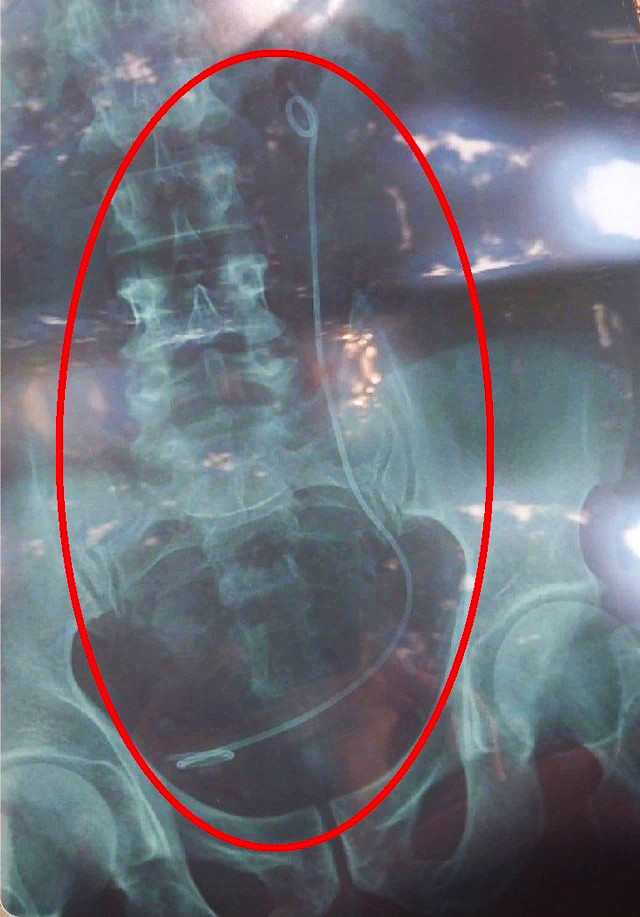

| Phim X-quang có sợi dây trong ổ bụng là của bệnh nhân khác nhưng trao nhầm cho ông Hải |

Khi có kết quả phim X-quang, bác sỹ Dương Xuân Kỳ (Khoa Ngoại Tổng hợp) đã khám, hỏi tiền sử bệnh của ông Hải và tư vấn bệnh nhân còn sợi dây ống trong niệu quản, do đó cần nội soi bàng quang chẩn đoán và rút sợi dây này ra qua đường nội soi. Thủ thuật này không phải mổ, ít xâm lấn và an toàn. Bệnh nhân đồng ý và ký cam kết thực hiện thủ thuật.

Quá trình nội soi bàng quang, bác sĩ Kỳ không tìm thấy sợi dây ống. Nghi ngờ có sự nhầm lẫn nên bác sĩ đã báo cáo với lãnh đạo khoa rồi trực tiếp dẫn bệnh nhân đi chụp lại phim X-quang. Kết quả, không có hình ảnh sợi dây ống trong niệu quản.